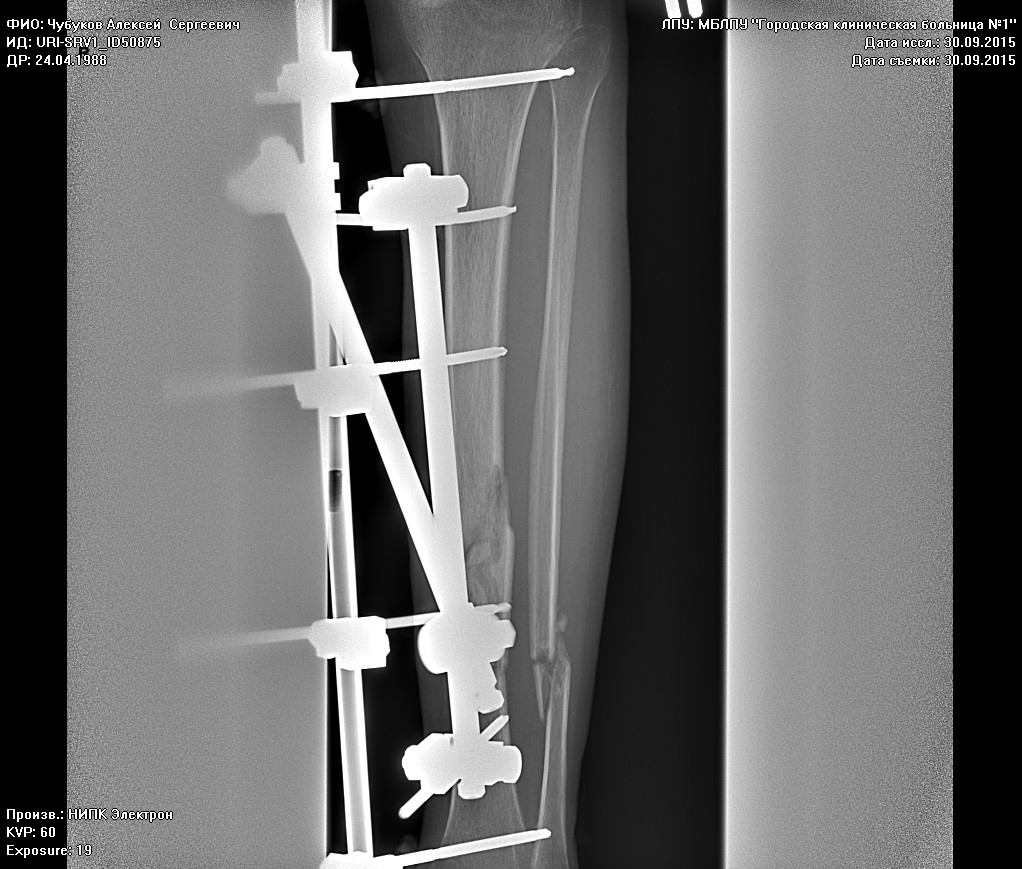

Вот такая конструкция теперь красовалась в моей ноге) В этот же день хирург пришел на осмотр, сказал, что можно вставать на костыли и давать нагрузку ноге до 20 кг. Плюс было назначено физиолечение (магнит), лечебная гимнастика.

А вы в такие малые сроки ничего и не увидите! Перелом голени в самых хороших случаях срастается за 3,5-4 месяца. Можете посмотреть мои снимки (пост выше), там даты есть. Я тоже задавал врачам вопросы по поводу малоберцовой кости, мне сказали не беспокоиться, всё срастется. хотя меня тоже гложут сомнения по этому поводу. А снимки у вас есть? Костная мозоль при пульпации прощупывается?